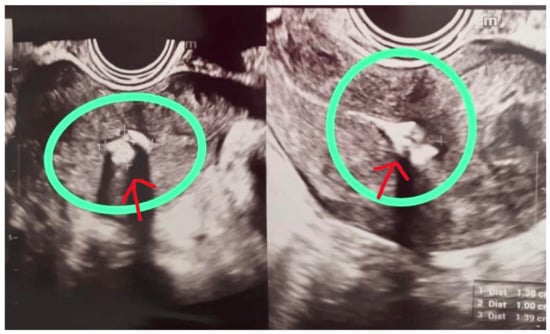

Upon entry into the uterine cavity, a 1.5 cm whitish, avascular residual amniochorionic fragment was identified on the right lateral wall. The surrounding endometrium appeared homogeneous, with no evidence of atypical vascularization, placental bed disruption, or signs suggestive of gestational trophoblastic disease.

The total operative time was 7 min, from insertion of the hysteroscope to removal. No intraoperative complications occurred, and no additional instrumentation was required (Figure 2).

Figure 2. Hysteroscopic view before (left) and after (right) resection of the amniochorionic tissue.